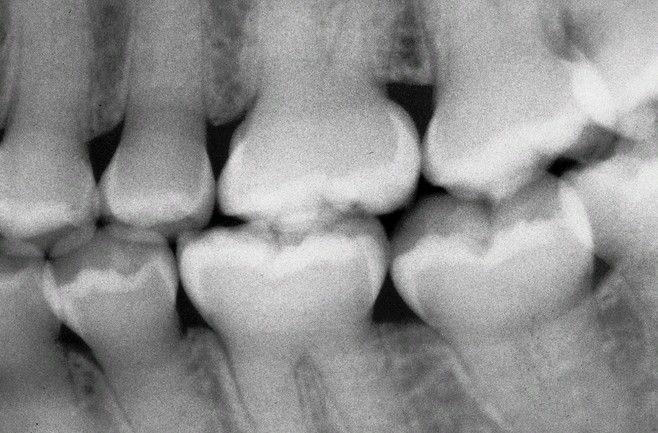

Dentinogenesis Imperfecta (DGI).

Radiograph of dentition exhibiting bulbous crowns, cervical constriction, and obliterated pulp canals and chambers.